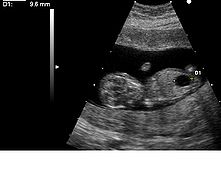

超音波顯示出一個患上唐氏綜合徵與巨膀胱的胎兒。正常染色體按照大小順序編號由1到22號,染色體早期的檢查中,曾誤認為唐氏綜合徵患者較大的染色體是第21對,其後的研究表明是源於較小的染色體的異常。但是為了不引起混亂,將第21對與第22對的名稱對調,現在繼續沿用“第21對染色體三體變異”這一名稱。